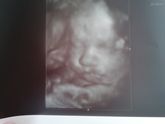

Нам 29 недель растём и набираем. По лицу маленькой моей зайки тауое ощущение, что папа в процесе не участвовал)))) тетя говорит, что вылетая наша бабушка(которой увы уже нет) одно конечно очень огорчило что есть обвитие. Врач конечно говорит, что еще … Читать далее